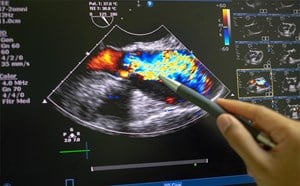

- Use both compression and color flow to ensure target is truly a vein

- Visualize the vein in cross-section (Fig. 3)

Figure 3. Short axis approach: vein visualized in cross axis